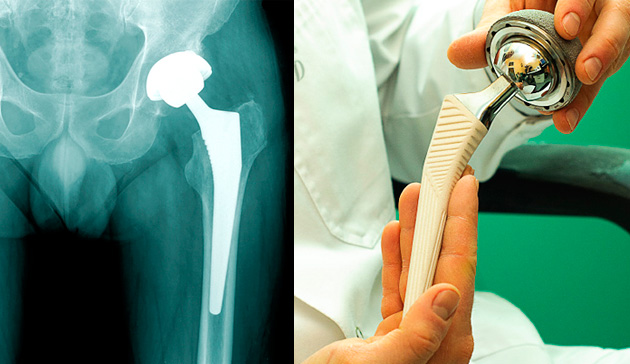

Эндопротезирование тазобедренного сустава: фото и схемы